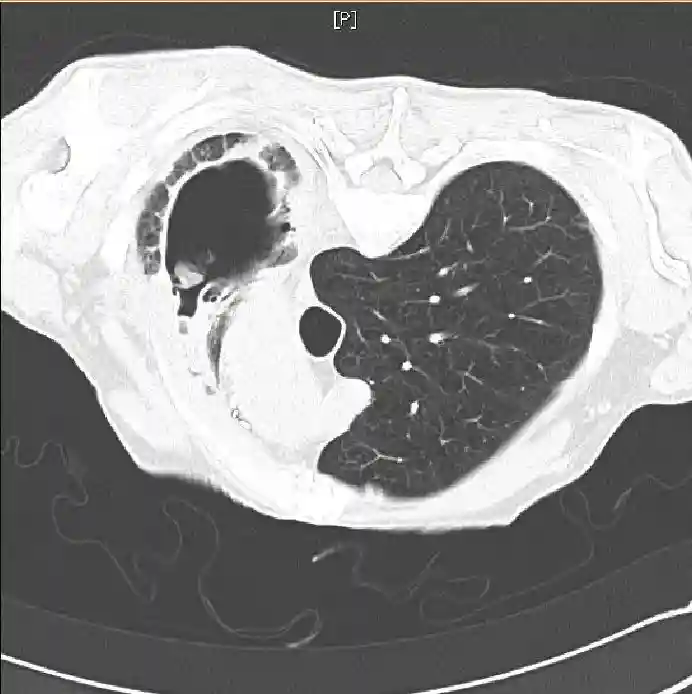

基于胸部X线片(图1)和计算机断层扫描(CT)(图2和3),做了进一步的实验室检查,并进行了支气管镜检查:

图3俯卧位CT扫描。

在放射学上,曲菌球在上叶明显,腔内肿块活动,周围有空气新月征。曲菌球的位置随患者位置的改动而变化。痰培养可能显示存在曲霉菌,但50%的病例培养阴性。几乎在所有的病例中,曲霉菌血清IgG抗体均为阳性;但是,在非烟曲霉所致的曲菌球患者或接受皮质类固醇激素治疗的患者中,可能出现假阴性。